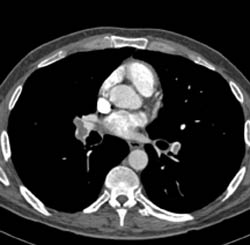

Diagnosis

Pe